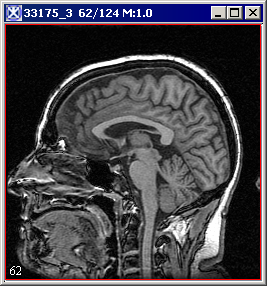

[2dHistogram.html#wp1556615 Figure 10] shows the two input images, the output 2D histogram image and its lookup table.

Figure 1. Two input images, output 2D histogram image and its lookup table